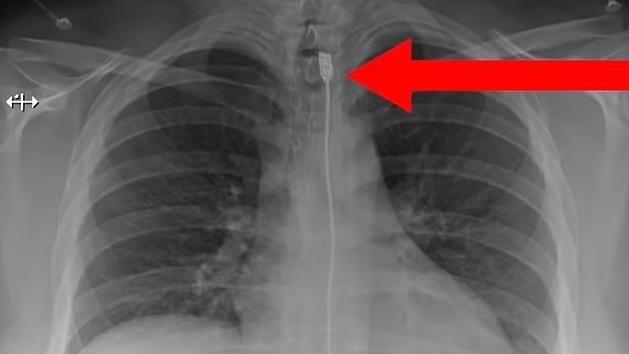

又一異食癖的誇張案例……英國《鏡報》等媒體報道,印度齋浦爾(Jaipur)一名34歲男子因劇烈腹痛、無法飲水進食,本月9日被家人送往醫院急症室就診。醫生替他做X光等檢查,驚見他食道裡竟卡著一隻手錶,大腸裡還有多塊鐵片、螺絲帽、螺絲、繩子、吊墜等物品,讓醫療團隊十分驚訝。